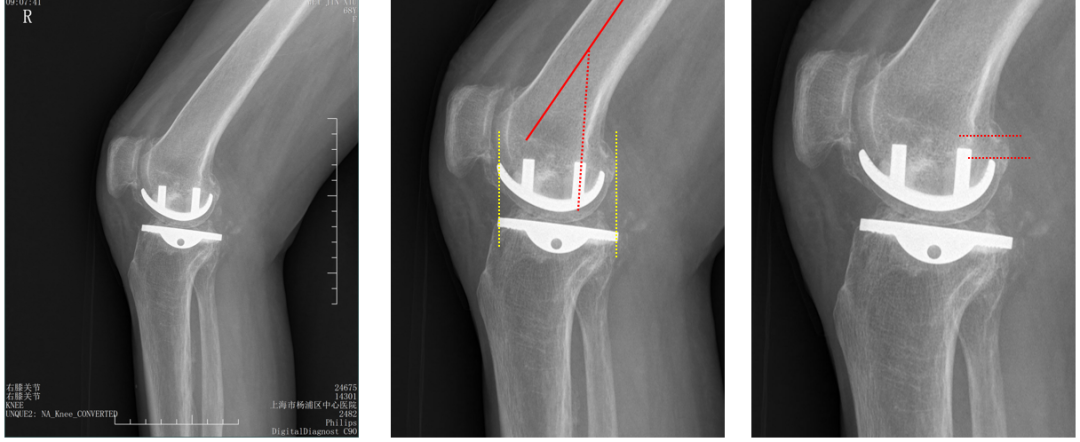

五、一期双单髁置换LINK:registered: SLED假体位置

双间室OA行Bi-UKA

正位片标准胫骨和股骨假体位置

AP位假体位置:内侧和外侧单髁分别按照各自的手术原则独立开展,假体的位置也按照各自的标准进行考量,需要综合考量的是胫股角,关节线,中央髁间隆突。

侧位片标准胫骨和股骨假体位置

侧位假体位置:内侧和外侧单髁分别按照各自的手术原则独立开展,假体的位置也按照各自的标准进行考量。

双间室OA行Bi-UKA术后内侧假体周围骨折ORIF